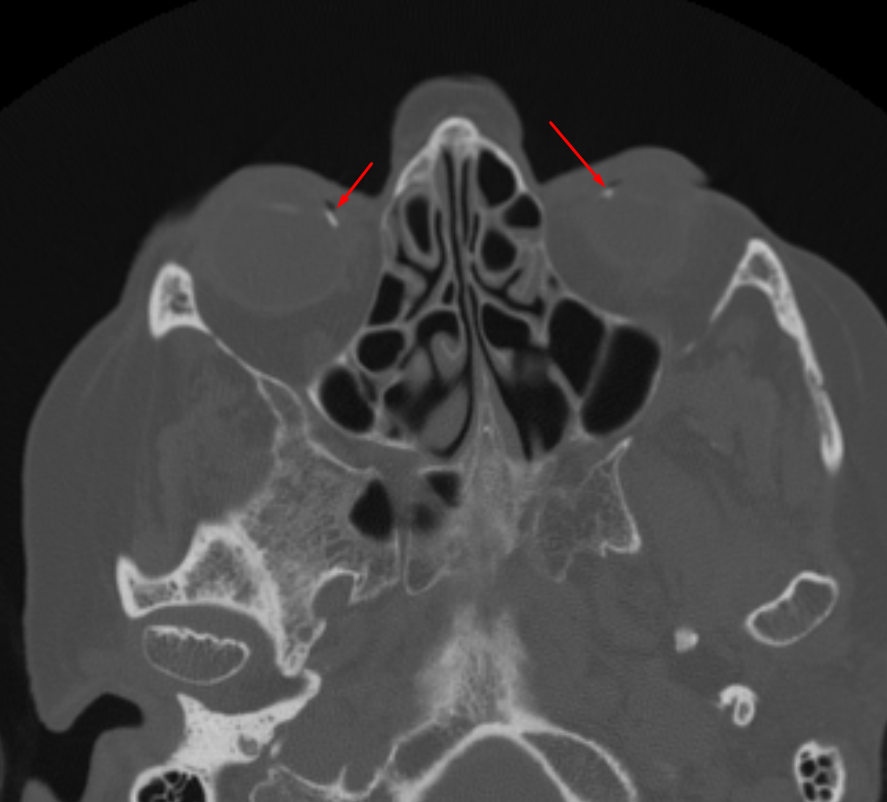

Age: 81

Sex: Male

Indication: Fall